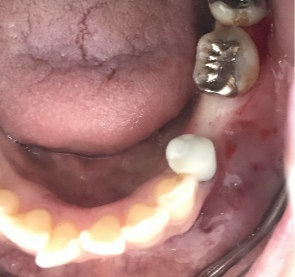

左下の抜けているところに歯を入れたい。

治療内容

インプラントを2本埋入しました。

所感

以前、1本歯がないところを、欠損の両側に被せ物をしてつないだブリッジでした。その2本のうちの前方の歯が歯根の破折を起こし、抜歯になり2本の欠損になりました。この2本の欠損を補う方法には、部分入れ歯、再度ブリッジ、インプラントの3つの方法があります。部分入れ歯もブリッジも欠損部分の負担をほかの歯に負わせるため、支台になった歯は負担が大きくなり、虫歯、歯周病、歯根破折の危険性が高まり、さらに歯を失うことになります。インプラントは、それ自身が単体で植立しているため他の歯に負担を負わすことがありませんので、咬合を回復させるだけではなく、他の歯を守る役割もあります。今回もX-Guideを使った埋入で、安心安全に行うことできました。

インプラント2本:¥363,000×2本=¥726,000(税込)

Before

After